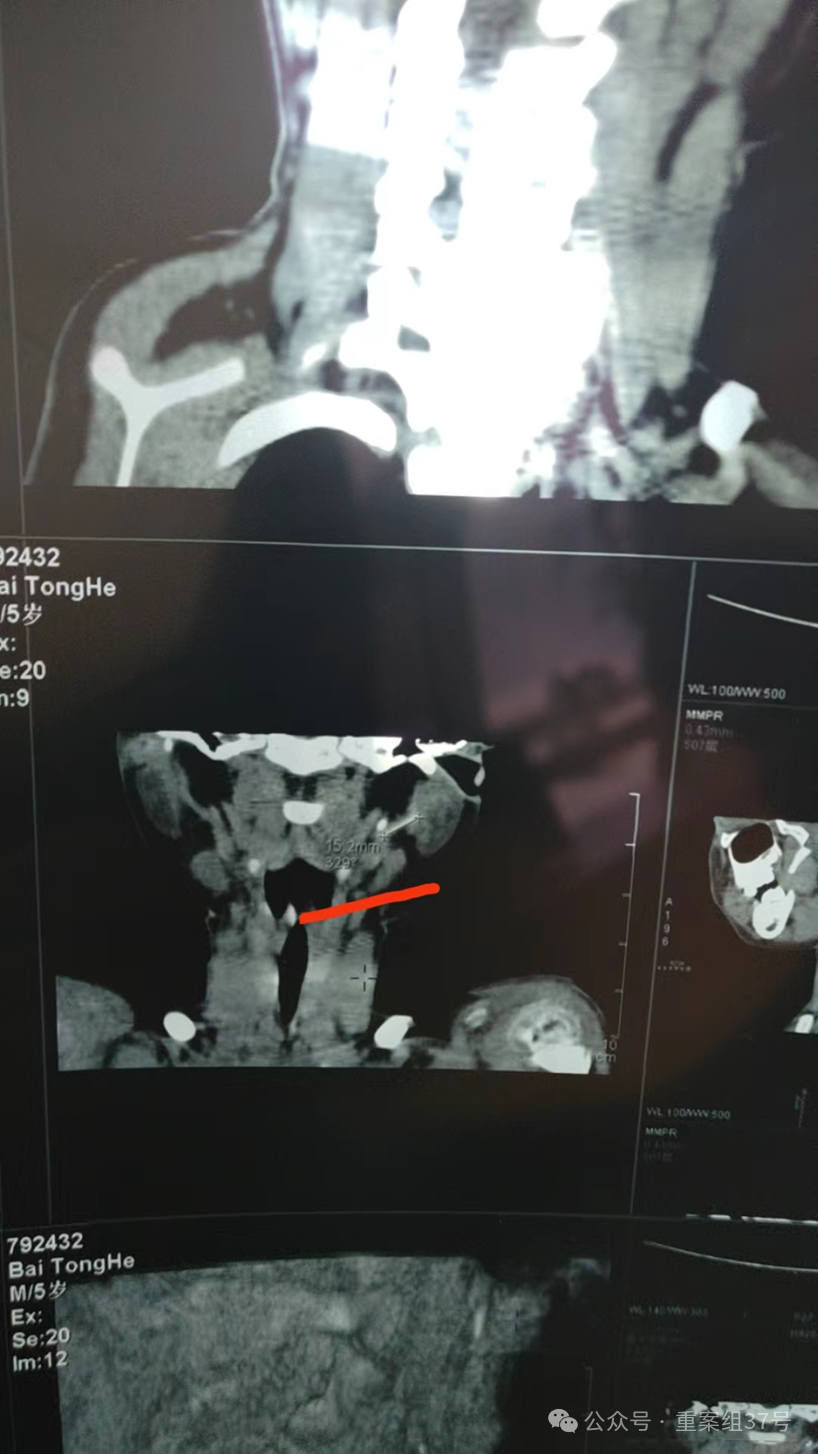

▲4月7日,星元医院CT结果显示,软管目前位于小白颈部左侧腮腺内。受访者供图